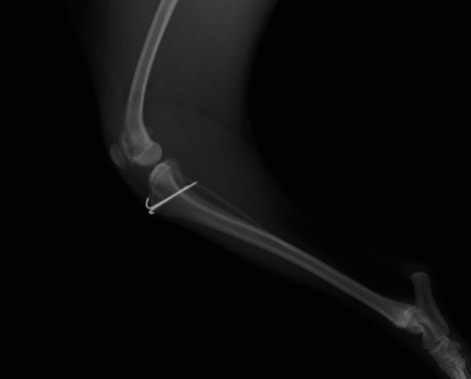

■ 症例22 ポメラニアン 1歳5か月 去勢雄

左後肢の挙上を主訴に来院した。整形学的検査、レントゲン検査より左右の膝蓋骨脱臼(左GradeⅡ〜Ⅲ、右Grade Ⅱ)を認めた。また、脛骨の前方引き出し試験の際に、引き出し兆候は認められないものの、疼痛が認められたため、前十字靭帯の損傷が疑われた。術中における、目視および関節内の操作によって、前十字靭帯の損傷や過伸展といった異常が認められなかったため、膝蓋骨脱臼の整復のみ実施した。手術手技は縫工筋及び内側広筋の解放、脛骨粗面の外側転位、滑車ブロック形造溝術、内外側関節包の縫縮を実施した。本症例は跛行もなく経過良好である。しかし、頸骨高平部の角度(TPA)が 右26.2°、左24.9°であり、解剖学的に前十字靭帯損傷のリスクが高いことから今後の経過に注意が必要である。